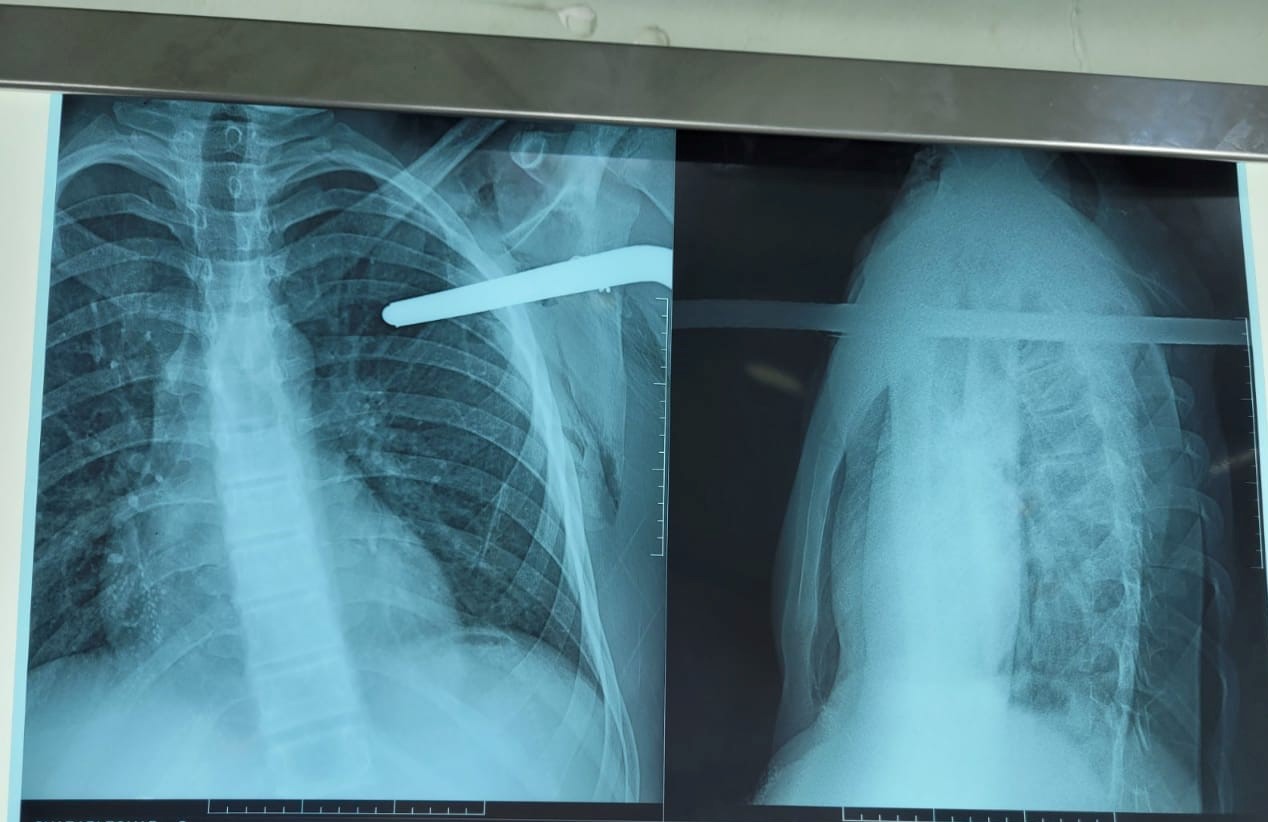

تمكن الطاقم الطبي لجراحة الصدر والأوعية الدموية بمستشفى مصطفى باشا الجامعي من إنقاذ شاب اخترقت قطعة حديدية صدره.

وكشف المستشفى في صفحته الرسمية عبر فيسبوك أن الشاب يبلغ من العمر 16 سنة ينحدر من مدينة سور الغزلان سقط من سطح المنزل واخترق قضيب حديدي جانبه الأيسر من الصدر.

وأضح المستشفى أن رجال الحماية المدنية قاموا بقطع القطعة الحديدية ونقله إلى المركز الاستشفائي الجامعي مصطفى باشا حيث تم التكفل به في مدة قياسية وحالته الصحية مستقرة.